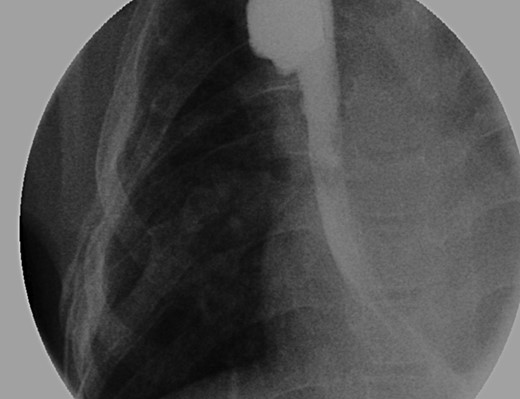

An intraoperative esophagram following a routine esophagogastroduodenoscopy (EGD) is pictured on the right, as compared with her postoperative esophagram on the left. The EGD was performed on this patient following her anastomosis (Foker Stage II); the native esophagus was now in continuity. Contrast was injected above the level of the anastomosis, which demonstrated neither leak nor stricture.